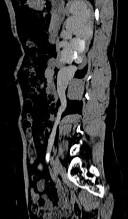

- 多项选择题患者女,44岁, 突发性胁腹部绞痛并向会阴部放射伴血尿一次。如图所示,下列说法正确的是 ( )

A、右侧肾盂肾盏扩张

B、右输尿管中上段扩张

C、右输尿管内可见沿输尿管走行的高密度影

D、右输尿管结石

E、左肾输尿管未见异常